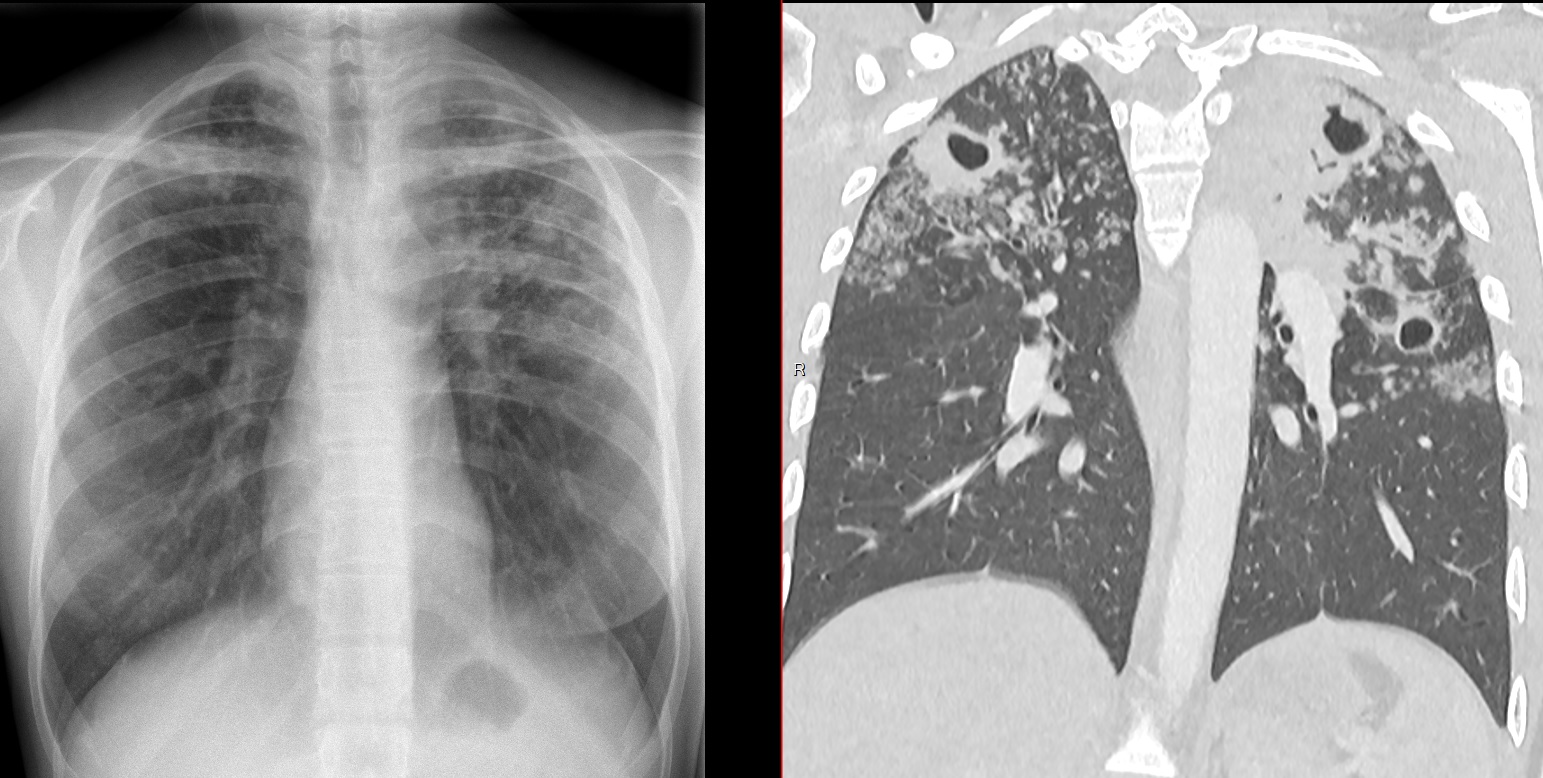

TB Miliaire

- Dans les TB primaires et Post-primaires

- Patients vieux, ou immunosupprimés

- Dissémination lympho-hématogène

- Rare mais mauvais pronostic

- Micronodules de 1-3mm de distribution aléatoire (hématogène)